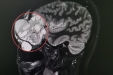

医生提醒,只有早期筛查、早期诊断,才能及时评估病情,有效控制血糖、减缓糖尿病合并勃起功能障碍的发生与进展。通过男性勃起功能相关检查,如夜间阴茎勃起与硬度监测、阴茎超声血流、阴茎海绵体造影、性激素等,结合血糖情况,评估勃起障碍类型和严重程度,有利于制定科学合理的治疗和康复方案。